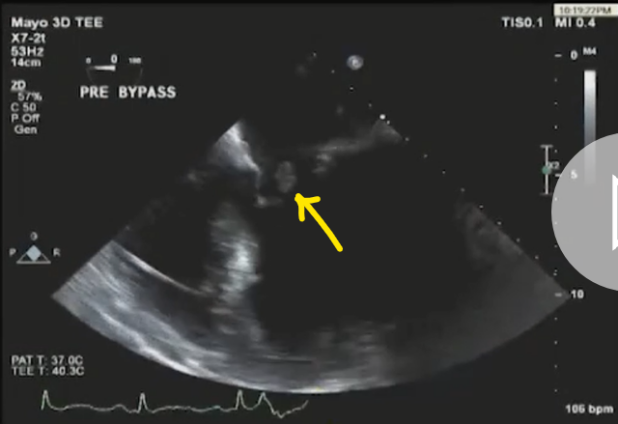

此培训为MAYO诊所推出的心内科fellow系列培训之一,主要目的是能够使大家学习到AMI以后心脏机械并发症的识别和诊断,还有ACS的非心脏的并发症的表现,以及临床中存在与ACS临床上有相似之处的非心脏疾病。 急性心肌梗死后出现的并发症,分为心脏性和非心脏性的,心脏并发症又包括心电学方面的并发症以及机械并发症,非心脏性并发症包括血栓栓塞和出血,还可能出现与心包相关的并发症。 心脏机械并发症包括就是破裂性和非破裂性的2类,破裂性并发症包括游离壁破裂、室间隔穿孔和乳头肌断裂,其中游离壁破裂既可能是直接的穿孔,也可以是亚急性破裂形成假性动脉瘤这样包容性的破裂。而非破裂性机械并发症包括严重的左室心力衰竭,右室梗塞,左室壁动脉瘤以及缺血性二尖瓣反流。 从根本上来说,这些严重并发症的发生都与心脏的泵功能衰竭有关,泵功能的衰竭造成了血流动力学不稳定以及基线的电不稳定性。 第一节:非破裂性机械并发症 非破裂性机械并发症,即严重的左室心力衰竭——心源性休克,右室梗塞,左室壁动脉瘤以及缺血性二尖瓣反流。 1、 心源性休克:在心梗发生时,发生心源性休克的主要原因就是大面积的心肌梗死,那么如果要导致心脏泵功能衰竭,左室心肌质量至少要损失40%以上。其他导致心源性休克的原因还有右室梗塞、心脏破裂以及快速和缓慢性心律失常。 2、 右室梗塞:也是导致心源性休克发生的重要原因。在下壁心梗的患者中,大概有33%的患者同时也发生右室梗死,这种情况多见于RCA近端闭塞,与高死亡风险相关。在所有下壁STEMI者中都要考虑是否同时存在RV梗塞,心电图V1和RV4导联ST段抬高超过1mm为其特异性心电图改变(图1)。 图1. 右室梗塞的心电图表现 3、 右室梗塞为什么会导致患者发生心源性休克呢?从病理生理上讲,右室急性缺血时会致其收缩不良,导致RV每搏输出量和峰压降低,继而是左室前负荷降低,心输出量降低;另一方面,急性缺血还同时使右室舒张功能受损,此时右心充盈压显著增加,并且由于右室急剧扩张,会在心包内占据很大体积,使得心包内压力显著增加,这些综合造成的结果使RV和LV的充盈减少。左心充盈压下降而右心压力不断升高,最终导致低血压、肺血流减少、颈静脉压升高,其临床结果可能类似于心包填塞以及缩窄性心包炎。 4、 左室壁动脉瘤(图2):首先提出一个问题供大家思考,以下有关左室壁动脉瘤的说法哪一个是正确的?1左室壁动脉瘤只局限于心内膜下;2有一个相对狭窄的颈部;3是否都与前壁心梗有关;以及4容易有血栓的附着,并且心包是组成瘤壁的一部分。实际上,左室壁动脉瘤在STEMI后的发生率<5%,前壁梗死的患者更易发生,及时进行再灌注治疗可以降低其发生率。它突出于心腔外侧,瘤壁就是左室壁,颈部和底部的比例大约是1:1,可以出现附壁血栓。所以上述说法中只有3是正确的。 图2. 左室壁动脉瘤示意图,O;颈部,D:底部,LA:左心房,LV:左心室,AO:主动脉 5、 缺血性二尖瓣反流:为心梗后左室重构所致,表现为乳头肌移位、乳头肌功能不良使瓣叶活动受限以及瓣环扩张(图3)。治疗的焦点集中于及时的再灌注治疗、利尿剂的应用和后负荷的降低,如果遗留严重的二尖瓣反流,则会导致心梗后的远期生存率下降。 图3. 瓣环扩张(A)、乳头肌功能不良致瓣叶活动受限(B)导致大量MR 第二节:破裂性机械并发症 破裂性并发症包括游离壁破裂、室间隔穿孔和乳头肌断裂,其中游离壁破裂既可能是直接的穿孔,也可以是亚急性破裂形成假性动脉瘤这样的包容性破裂。大多数破裂性并发症都发生在AMI的第一个24小时之内,剩余的则发生在1周之内。通过超声心动图可以发现MI的机械并发症,包括急性乳头肌断裂、下段室间隔断裂、上段室间隔断裂以及二尖瓣脱垂。 1、 乳头肌断裂所致二尖瓣反流(图4):乳头肌断裂常发生在MI后的2~7天,急性缺血事件发生时,从心外到心内的压力梯度增加,心内灌注降低,乳头肌属于心内结构,缺血的敏感性增加。一旦出现需要外科手术治疗。 图4. 乳头肌断裂(箭头所示) 2、 室间隔缺损(图5):属于MI后的罕见并发症,多于梗死后3~5天发生,在梗死后即刻或者第一个24小时内就可以发生,部分与患者进行的纤溶治疗有关。由于再灌注治疗的开展,目前发生率已经由2%降至0.2%。破裂发生在健康心肌和坏死心肌的交界处,在前壁心梗时,缺损位于室间隔心尖部,下壁心梗时缺损则位于下-后间隔基底段,RV梗死及功能失常者预后不良。 图5. 前壁心梗(A)、下壁心梗(B)所致不同部位室间隔穿孔 3、 游离壁破裂:急剧的、常为致死性机械并发症;发生率<1%;MI后死亡约8~24%是由此而造成;通常在梗死后的5天内发生。好发因素包括1首次心梗,2前壁心梗,3老年患者以及4女性。 4、 亚急性破裂:是一种特殊类型的游离壁破裂,占所有游离壁破裂患者的约1/3,是因为附壁血栓和心包覆盖了穿孔部位所致,局部表现为假性动脉瘤(图6),临床上常比较隐匿,并且可能仅通过UCG发现,因此任何超声发现的心脏周围局部积液都需要引起怀疑并详细扫查。与真性动脉瘤(即左室壁动脉瘤)不同,假性动脉瘤的颈部狭窄,颈部与底部的比值<0.5,心包是瘤壁的组成部分。亚急性破裂的进展常是难以预测,可以进展至完全破裂乃至心包填塞,因此需要外科治疗。 图6. 左室假性动脉瘤示意图,O;颈部,D:底部,LA:左心房,LV:左心室,AO:主动脉 第三节:AMI的非心脏并发症 AMI的非心脏并发症主要包括血栓栓塞和出血,以及心包并发症。那么下面关于左室血栓的说法哪个是正确的呢?1下壁心梗更为常见,2如果不予治疗栓塞风险可达50%,3栓塞的风险取决于血栓的移动性和是否凸出于腔内。左室血栓常(图7)见于大面积前壁心梗,在再灌注前时代其发生率可高达40%,有再灌注治疗后这一几率已降至4~15%;经胸超声心动图是发现LV血栓的第一选择;心脏MRI的敏感性更高,但与超声心动图的特异性相似。由于心梗后不运动和运动障碍的室壁区域存在静止血流,因此如容易在局部形成附壁血栓。如果梗死部位为心尖部,且左室EF值减低达<30%,则存在血栓栓塞的高风险。如果未治疗,左室血栓发生栓塞的风险为10~15%,这一风险的高低还取决于栓子的移动性和是否突出于心腔内,早期且持续的抗凝治疗(3~4个月)可以降低栓塞风险。 图7. 左室心尖部附壁血栓 一图总结心脏机械并发症 第四节:类似ACS的非心脏疾病 通过一个有趣的病例,我们来学习一下在临床中可能存在类似于ACS表现的非心脏疾病。这是一个77岁老年女性,症状为头晕、恶心、呕吐,急诊CT除外了急性卒中,但心肌坏死标记物升高,心电图提示为Af、并且下壁前壁导联T波倒置,但超声心动图上仅表现为室间隔中下段至左室心尖部运动减低,没有看到下壁及前壁的运动异常。随后患者出现严重的高血压和心动过缓,并存在定向力、消化不良和眼球震颤,继续监测头CT及MRI,结果发现枕叶大面积脑梗。实际上,早在1947年,急性卒中所引起的ECG变化就已经被报道,病程中出现深大的倒置T波则被称为神经源性T波。在急性颅内事件发生时可以存在肌钙蛋白的升高以及心电图出现ST-T改变,在卒中的急性期,ECG诊断急性心梗的特异性会降低。 除急性脑血管病以外,以下疾病也会出现类似于ACS的临床发现,包括心电图异常和心肌坏死标记物升高,如特发性应激性心肌病,主动脉夹层,肺栓塞等等,需要及时进行诊断及鉴别诊断。 最后需要强调的是,超声心动图是发现AMI后心脏机械并发症的最重要检查,AMI发生后一周内必须行UCG检查以发现隐匿的高危并发症。